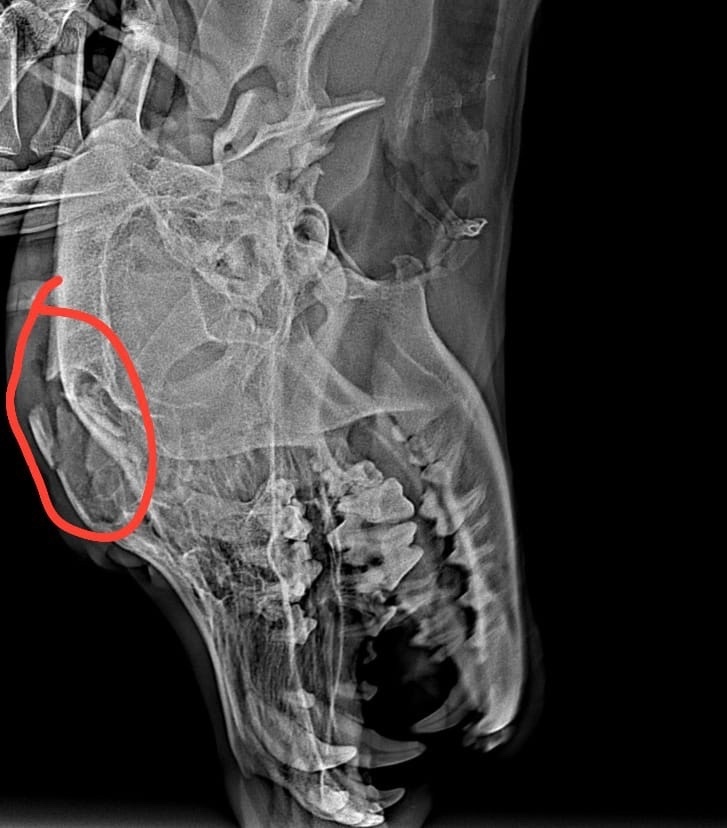

Открытый перелом нижней челюсти, костные обломки зияют в ротовой полости. Паралич задний конечностей, ПРИЧИНА НЕ УСТАНОВЛЕНА, возможно из-за ЧМТ. Позвоночный столб по рентген снимкам без видимых повреждений. Это все, что нам удалось выяснить и на что хватило денег. Снимков делали много, так как и челюсть и позвоночник проверяли. 7 штук вышло 8 400 рублей. ЭТО ОГРОМНАЯ СУММА, которой порой и в семье нет, а что говорить о приюте, где 500 бездомных таких же животных…